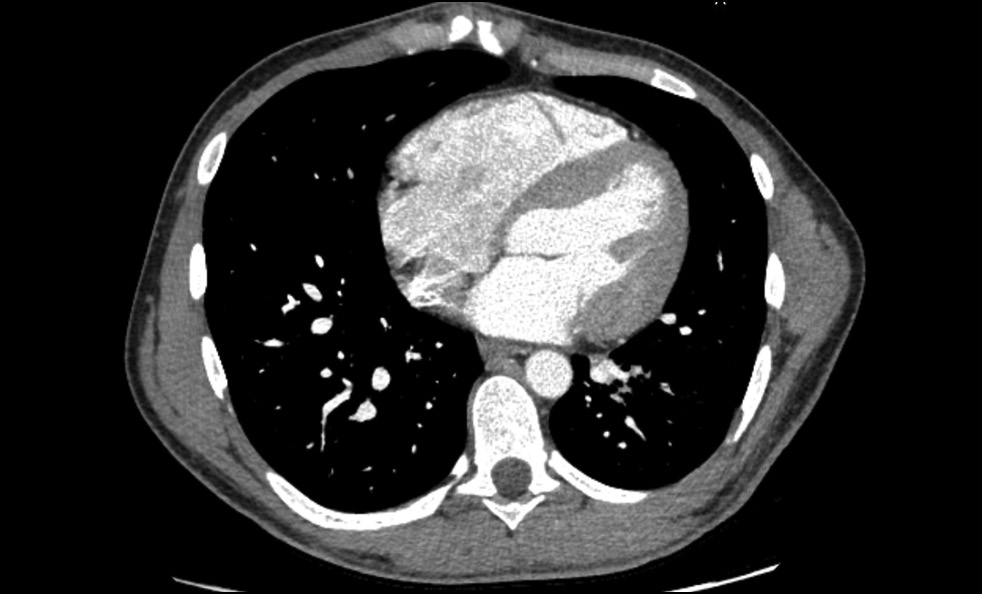

Contrast-enhanced abdominal computed tomography (CT) with multiplanar reconstruction revealed that the splenic (12 mm in diameter (Figure 1)) and superior mesenteric veins fused together, forming a portal vein conduit dilated to 28 mm in diameter (Figures 2 and 3), flowing directly into the inferior vena cava (IVC), bypassing the porta hepatis (Figure 4). Moreover, moderate liver and spleen enlargement and weak heterogeneous contrast enhancement of the liver parenchyma were noted. The findings were consistent with Abernethy malformation type Ib.

Fig. 1. Contrast-enhanced CT, portal phase, axial view. Dilated splenic vein (SV).